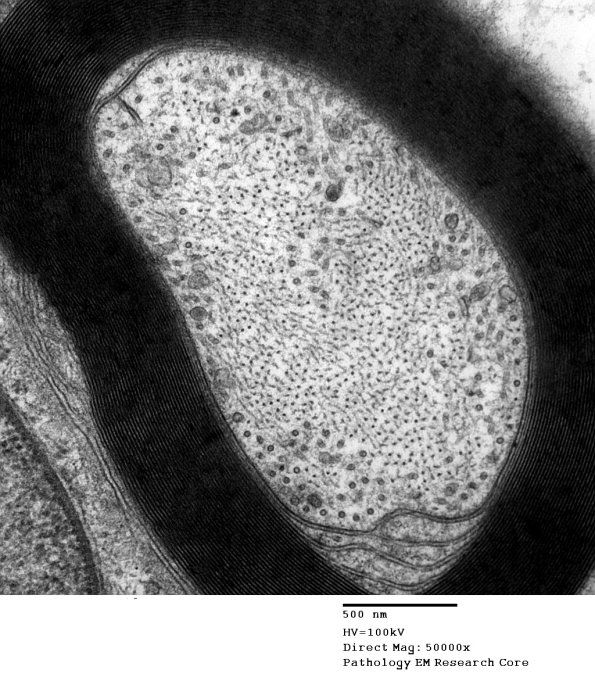

Ultrastructure ----- Ultrastructural examination provides a detailed look at the subcellular composition of individual axons and pathologic processes. Unmyelinated axons, which are 3-4 fold more numerous than myelinated axons in the sural nerve, range in diameter from 0.2-2.0 microns and are difficult to appreciate purely with light microscopic techniques. ---- 1A This small myelinated axon exhibits a wealth of neurofilaments and microtubules, typically referred to as the axonal cytoskeleton.